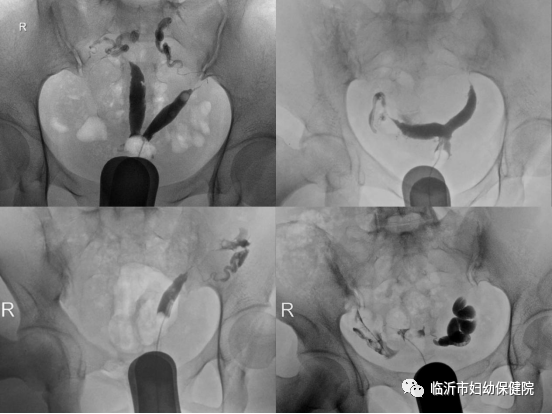

输卵管是连接子宫与卵巢的一根细长的管,是受精的部位也是受精卵能够回到子宫的重要通道。如果输卵管出现异常,会让女性受孕的概率大大降低。输卵管造影是通过导管向宫腔及输卵管内注入造影剂,在X线透视下摄片,根据造影剂在子宫、输卵管及盆腔内的显影情况来了解输卵管是否通畅、梗阻部位及宫腔形态的一种检查方法。

正输卵管造影的图像:可清晰显示子宫、输卵管形态

各种子宫畸形、输卵管梗阻积水